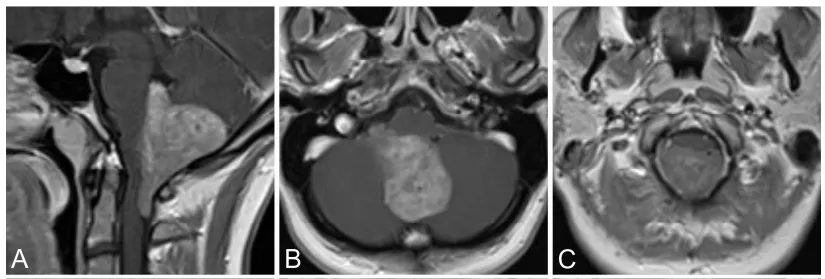

29岁珍妮,因右侧头痛、颈部及手臂痛1年就诊。MRI示第四脑室内巨大均匀强化肿物,向下延伸至C2水平(图1A–C)。

临床查体未见明显异常,无脑积水征象。术中在神经电生理监测下行全切除术。术后短暂出现右手轻度失用,数周后恢复,无永久性神经功能缺损。

术后即刻及14个月随访MRI均未见肿瘤残留(图1D–I)。